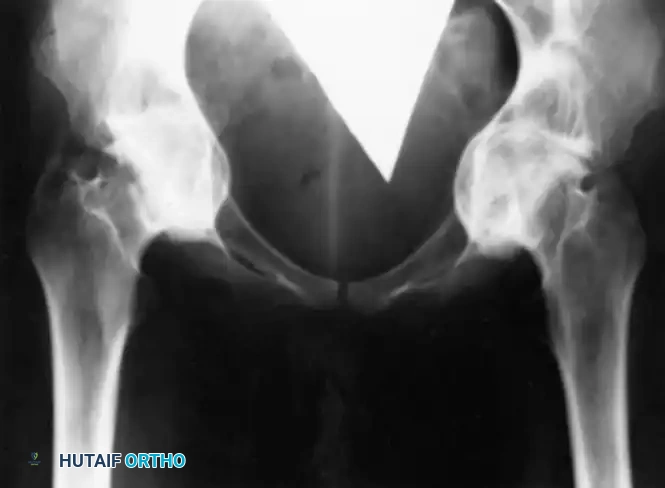

Intrapelvic protrusio acetabuli, historically referred to as Otto pelvis or arthrokatadysis, is a complex morphological deformity characterized by the chronic, progressive protrusion of the femoral head into the acetabulum and the true pelvis. Radiographically, it is defined by the medialization of the acetabular line past the ilioischial line (Kohler’s line).

Standard anteroposterior (AP) pelvis and lateral hip radiographs are essential. The diagnosis is confirmed when the acetabular teardrop is obliterated or when the medial wall of the acetabulum projects medial to Kohler's line.